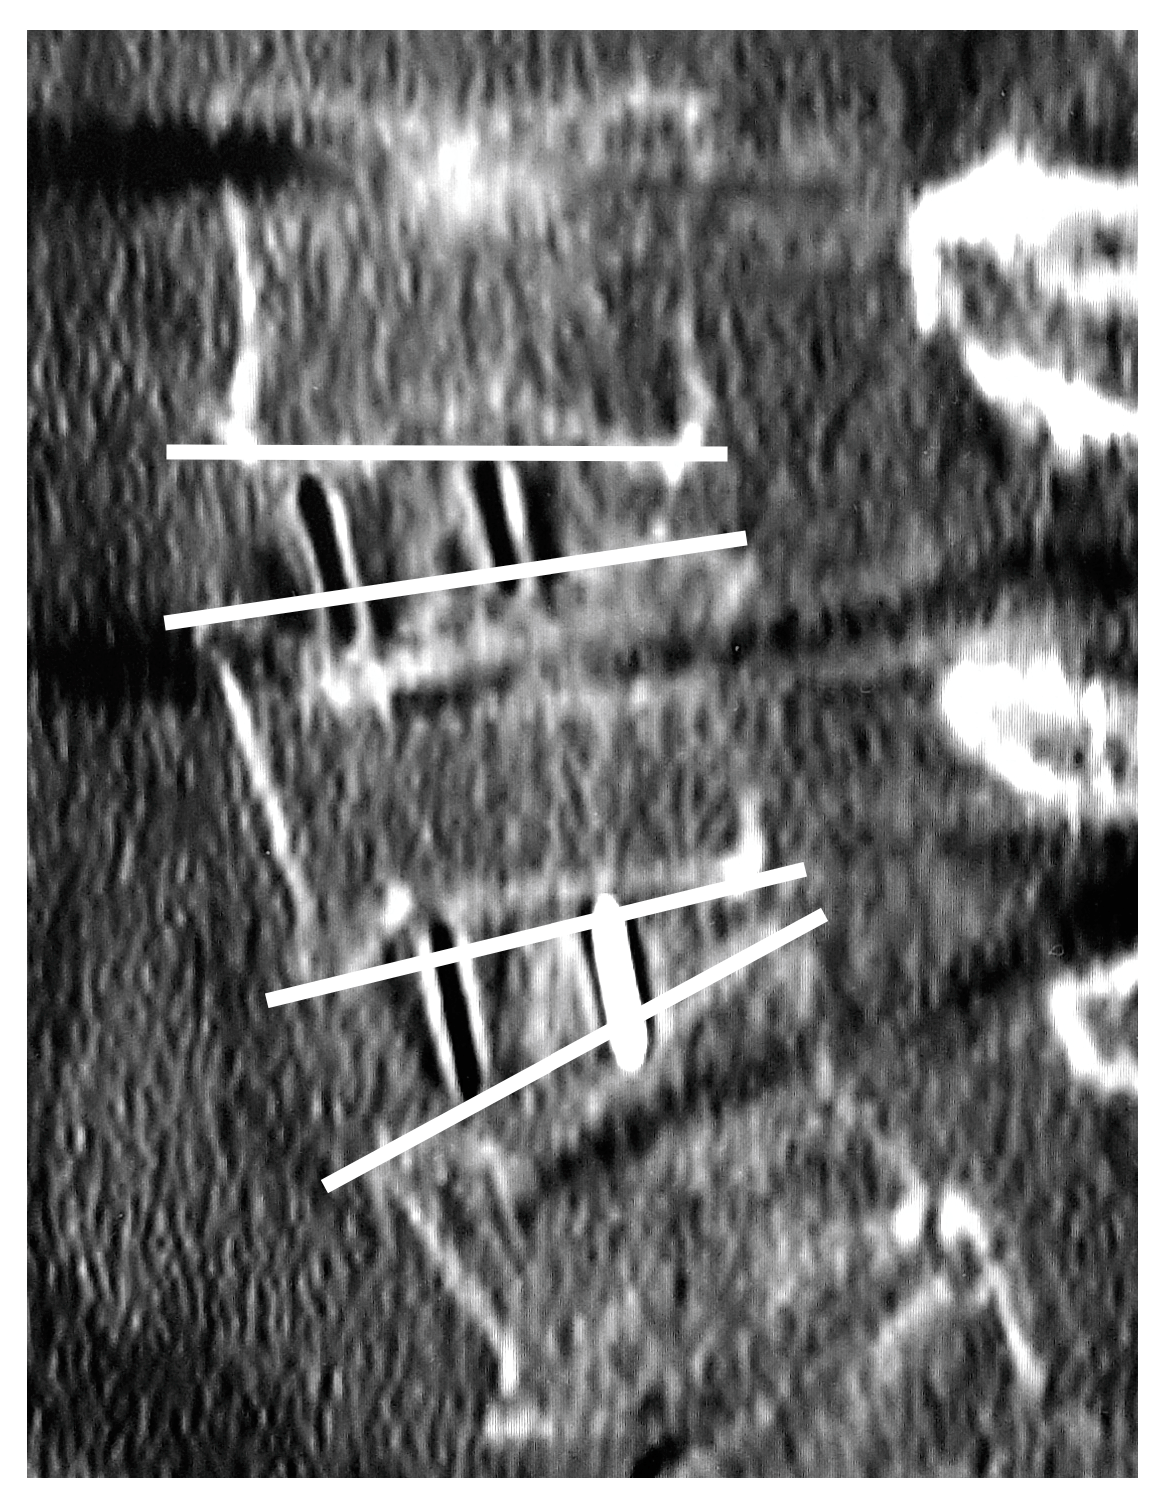

2.5. Vertebral Endplate Concavity (VEC) and Cage Subsidence

| VEC | |||

| Post-op | 2 (8.0%) | 17 (45%) | 0.002 |

| 3 months progression | 0 (0%) | 8 (21%) | 0.019 |